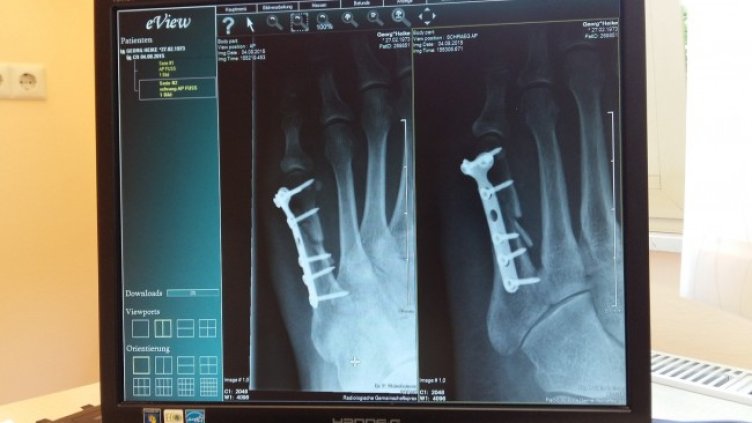

„Приблизително една от всеки три жени и един от всеки пет мъже над 50-годишна възраст получават остеопоротична фрактура до края на своя живот. Най-опасни са бедрените фрактури. Две трети от тях са при жените, а една трета – при мъжете. Смъртността от бедрени фрактури при представителите на мъжкия пол обаче е по-висока. Всяка четвърта жена (около 25%) и всеки трети мъж (около 35%) умират в рамките на една година, след като получат бедрена фрактура. Статистиката показва, че бедрените фрактури се нареждат на четвърто място след исхемична болест на сърцето, деменцията и рака на белия дроб. Рискът от счупване на бедрото при жените е по-висок от опасността от развитие на рак на гърдата, ендометриума и яйчниците взети заедно. 60% от пациентите с бедрена фактура остават до края на живота си в нужда от чужда помощ, а 20% - с тежка инвалидизация. Но има спасение. Това е ранната диагноза и ранното лечение“, сподели д-р Родина Несторова по време на пресконференцията по повод старта на кампанията „Не се пречупвай!“.